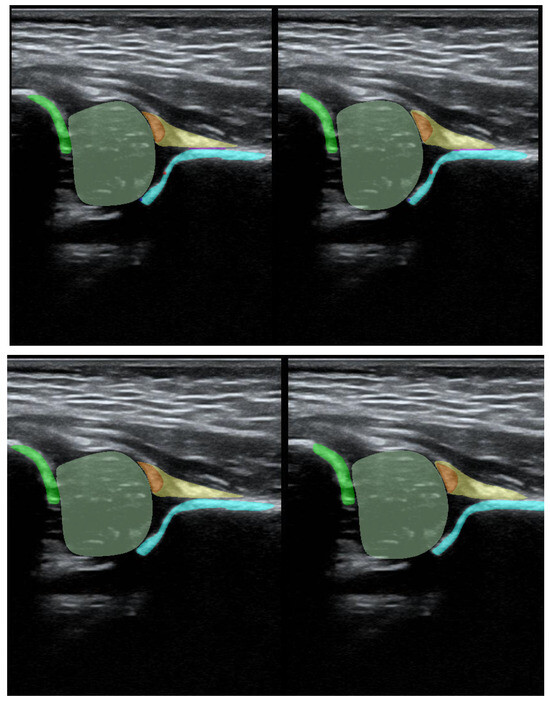

Additionally, during the model training process, the PaddleSeg library uses various pre-processing techniques (e.g., Resize, Normalize) and augmentation techniques (e.g., RandomHorizontalFlip, RandomDistort), which were also used in our training. The first step of pre-processing involved cropping the images to the ultrasound area to eliminate regions that do not pertain directly to the ultrasound scan. The second step involved the preparation of masks containing only 5 classes (chondro-osseous border, femoral head, labrum, cartilaginous roof, and bony roof). This step was performed to create the input for Model-5 (Figure 2).

Figure 2. Result of pre-processing: extracting the USG area from the image and preparing masks for Model-5 (lower picture) and Model-8 (upper picture).

Jcm 14 06332 g002